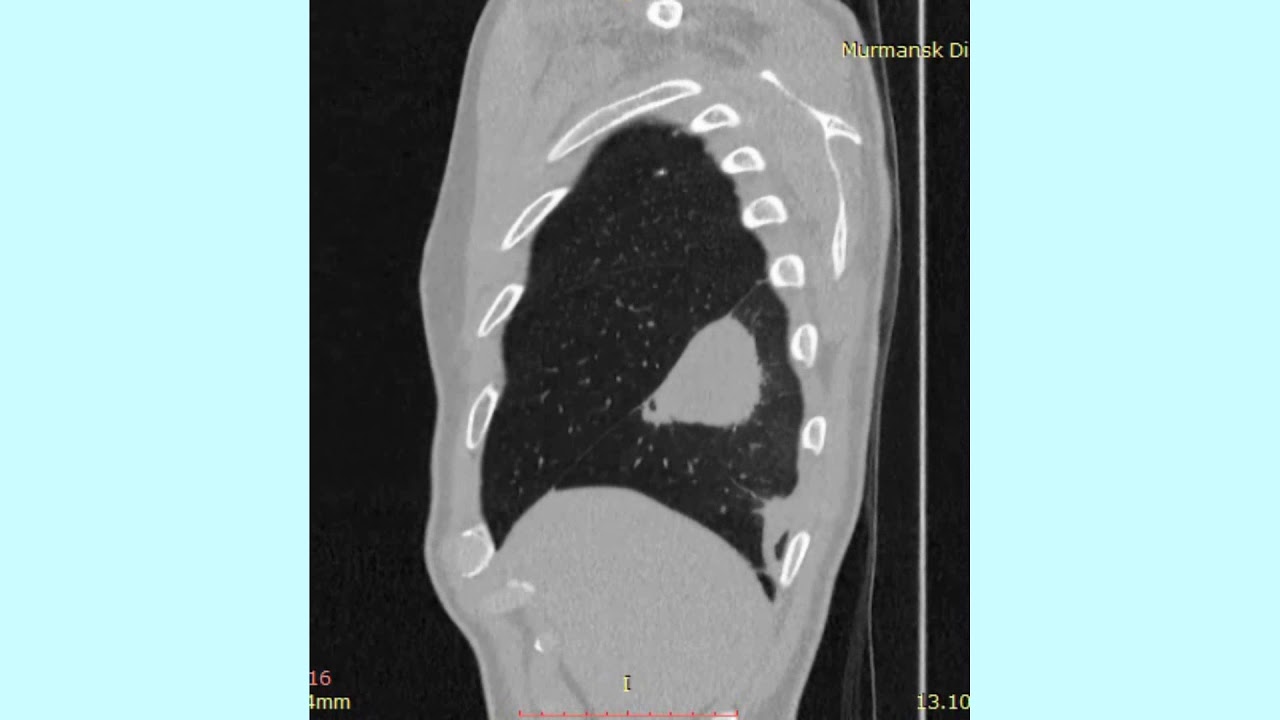

Это связано с тем, что, в отличие от бактериальных пневмоний, микоплазменная и хламидийная не имеют отчетливых физикальных и рентгенологических признаков инфильтрации, а культуральная диагностика их невозможна, так как микоплазмы и хламидии являются внутриклеточными возбудителями.

Поэтому диагностика микоплазменной и хламидийной пневмоний основывается в первую очередь на выявлении особенностей клинико-рентгенологических данных и подтверждается серологически или с помощью полимеразно-цепной реакции (ПЦР).

- отсутствие четких проявлений на рентгенограмме;

При появлении признаков пневмонии нужно обратиться к доктору. На осмотре врач послушает пациента и выявит сухие или влажные хрипы. Рентгенография грудной клетки не поможет определить заболевание. Аппарат покажет, что легкие воспалены и увеличены. К такому признаку могут привести разные заболевания. Поэтому чтобы выявить такой тип патологии пациент должен сдать определенные анализы.

Происходит это потому, что микоплазменная пневмония не имеет четких физикальных и рентгенологических признаков инфильтрации.